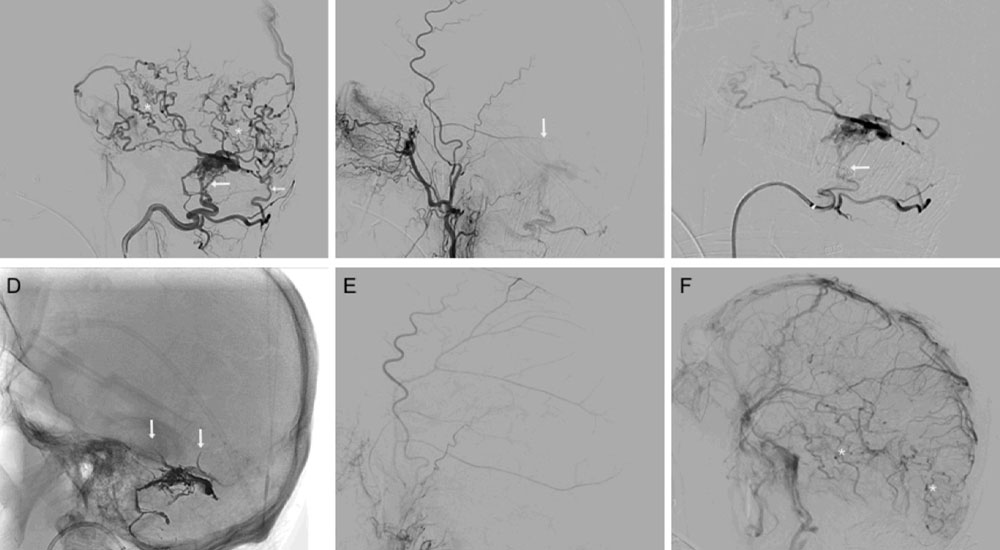

Endovascular embolization is the most common form of treatment for an AVF. We perform this procedure by inserting a catheter into an artery (usually the femoral artery in the front of the hip). Then, guided by fluoroscopic or X-ray imaging, we move it to the location of the fistula. We inject contrast so that we can see the exact location of the AVF. Then we inject material into the exact location where the artery and the vein meet, to stop the blood flow. We use a variety of types of devices, including coils, detachable balloons, embolization glue, embolization particles, embolization material (called Onyx), and vascular plugs. Once we have closed the connection between the artery and the vein, the AVF is cured and usually does not reoccur.

Occasionally, when the fistula happens between the side of an important artery and the vein next to it, we insert a covered stent (a wire mesh tube covered with fabric) into either the artery or the vein. This technique typically cures the AVF while keeping the artery and vein intact. A third option is to surgically close the fistula.